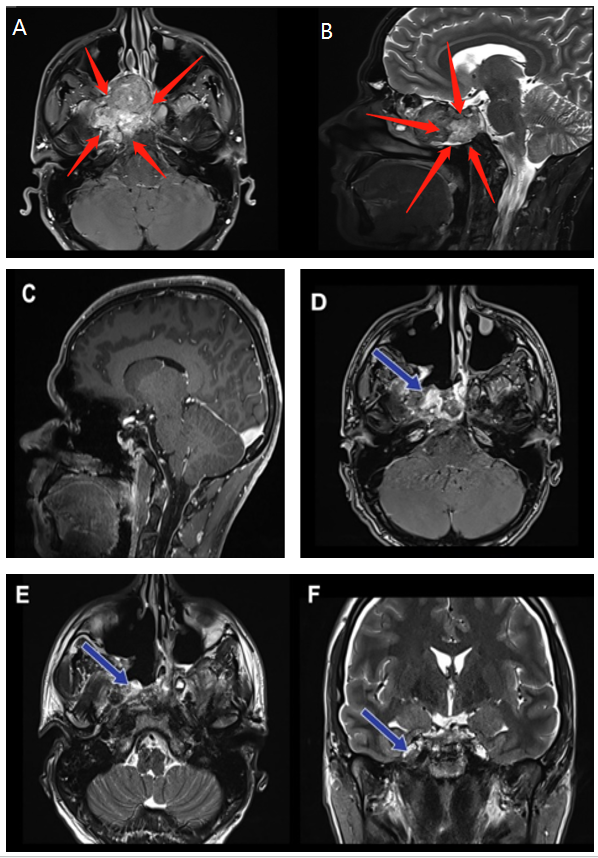

脊索瘤是一种低度恶性骨肿瘤,发病率约为0.08/10万。颅内脊索瘤在斜坡上的发病率较高。Mefty等报道称,颅内脊索瘤累及斜坡的发病率为93%,通常位于中上...

体重仅18kg的6岁小孩林林,400g不到的大脑里却长了近7cm苹果大的肿瘤,要怎样尽量微创的手术才能为弱小的身躯摆脱肿瘤还是棘手的较大颅底脊索瘤、包裹...

显微镜开颅与经鼻内镜联合手术技术,可结合显微镜下的开颅手术精确性与经鼻内镜技术的微创优势。INC国际神经外科教授福洛里希运用过该技术,成功治...